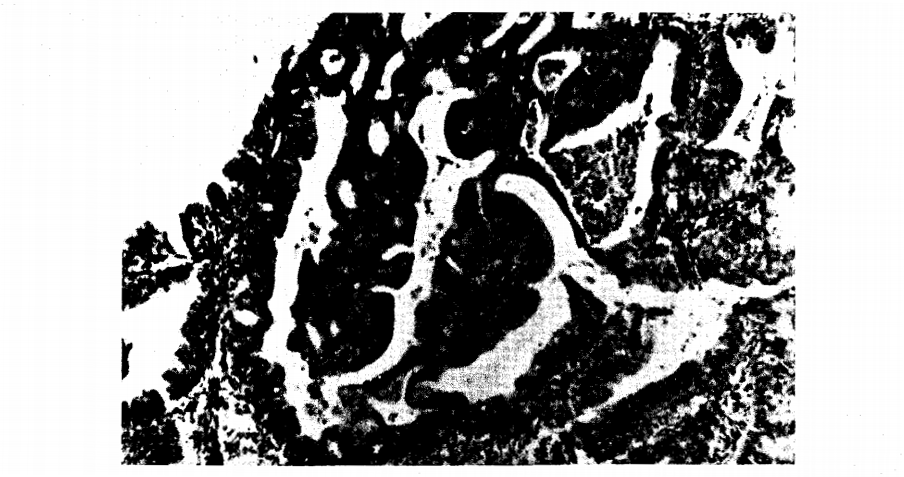

Figure 8. Atypical adenomatous hyperplasia, diagnosed by some pathologists as carcinoma m situ.

Figure 9. Same patient as in Figure 8. Note change to secretory endometrium after 200 mg of Norelutate divided over five days.